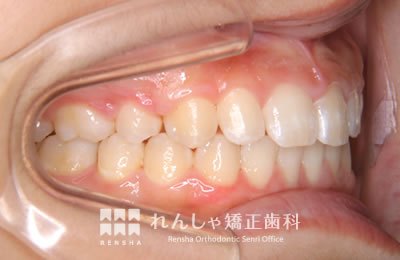

中高生

永久歯列はほぼ完成してしますが、歯列を側方だけでなく後方へも拡大し、埋まっていた右上奥歯を引っ張り出しています。

| 主訴 | 埋まったままでてこない歯がある |

|---|---|

| 診断名 | Angle Class II 小臼歯の埋伏と叢生を伴う上顎前突 |

| 初診時年齢 | 13歳5か月 |

| 装置名 | マルチブラケット装置 |

| 抜歯非抜歯 | 非抜歯 |

| 治療期間 | 2年3か月 |

| 費用の目安 | 約82万円+消費税(検査料金、都度の処置費用等も合わせた総額) |

| リスク副作用 | 歯の移動に伴う軽微な歯根吸収、歯槽骨吸収、歯肉退縮(本症例では軽度の歯根吸収を認めた)、矯正器具装着中のカリエスリスク増大(本症例ではカリエス発生無し) |